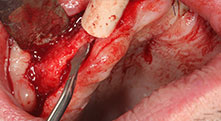

Could you describe briefly, for example, your procedure for mobilizing bone blocks for transplantation?

Bratu: We prefer to harvest bone from the external oblique ridge of the posterior mandible, not from the interforaminal region. After the soft-tissue incision, we use the new saws to define the amount of bone to harvest. With this approach, we also use them for the entire preparation in almost 80% of cases. We may also use other piezo instruments and then at the end a chisel to mobilize the block. We find that this is a very effective surgical technique.

Could you give us a few surgical tips and tricks from your hospital?

Bratu: We like to use the sandwich technique for augmentation in the lateral mandible. A bone cover is prepared with the piezo saw and the crestal fragment is fixed with microscrews. We place a mixture of autologous bone and xenogenic bone replacement material in between. This works very reliably. You should always ensure sufficiently dimensioned vertical cuts when splitting the alveolar ridge in the mandible. Otherwise the bone may fracture easily.

Bratu: I consider piezo surgery a great leap forward in oral surgery. The technique makes bone preparation safer and easier. Little bone is lost, for example in extractions. This is very important in the aesthetic zone, particularly if immediate implantation is planned. Piezo surgery is also safer for soft tissue: injuries to membranes in the sinus are basically history, as are nerve injuries when bone blocks are being harvested. Data indicating reduced postoperative swelling and pain are also available. Piezo surgery is also ideal for preparation of sinus septa. And last but not least, our patients benefit from the atraumatic nature of this technology.